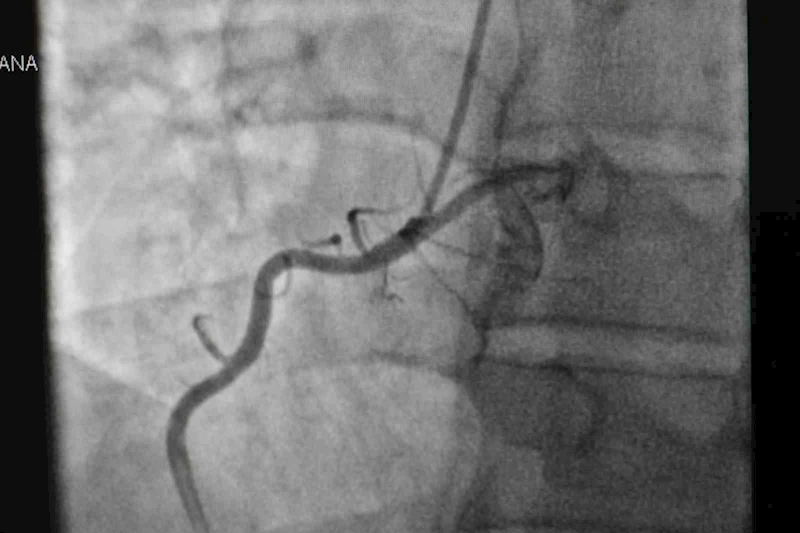

Anestezi olmadan yapılan görüntüleme ve damar açma tekniklerinden de bahseden Uzm. Dr. Ahmet Yanık, "Kalp hastalıklarının en büyük belirtisi göğüs ağrısı, nefes darlığı, çarpıntı ve bayılma gibi şikayetler olur. Göğüs ağrısını birçok hastalık yapabilir. Kalp hatalığında göğüs ağrısı genelde göğsün orta kısmında çeneye veya sol kola yayılan, yaklaşık 10-15 dakika süren bir baskı, yanma şeklinde olan ağrıdır. Böyle ağrı ve yanması olanların kalp yönünden muayene olması gerekir. Hastaları muayene ederken fizik muayenenin yanı sıra EKG'lerini görüyoruz, ekokardiyografi yapıyoruz. Gerekli hastalarda efor testi ve bazı tetkikler yaparak damarlarda bir tıkanıklık var mı bunu buluyoruz. Eğer kalp damarında bir tıkanıklık bulursak o zaman koroner anjiyografi yapıyoruz. Koroner anjiyografi 10-15 dakika sürecek bir işlemdir. Hastalara anestezi vermeden el bileğinden ya da kasıktan anjiyolarını yapıp, kalp damarlarını görüntülüyoruz. Bu yöntemle kalp damarlarında bir tıkanıklık buluyorsak ve açılması gerekiyorsa genellikle aynı esnada balon ve stent işlemi ile damarlarını açıyoruz. Bazen çok ciddi ve fazla stent gereken darlıklar olabiliyor. Öyle durumlarda da hastaya bypass ameliyatı gerekebiliyor. O zaman da hastaları bypass ameliyatına yönlendiriyoruz" diye konuştu.